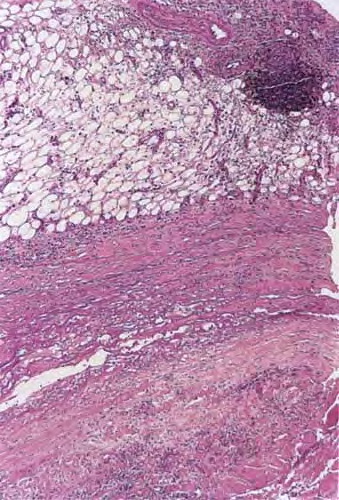

Histopathology

. A deep wedge biopsy to skeletal muscle including fascia is essential to making the diagnosis of eosinophilic fasciitis. The fascia is markedly thickened, appears homogeneous, and is permeated by a mononuclear inflammatory infiltrate . In some instances the infiltrate in the fascia contains an admixture of eosinophils . The underlying skeletal muscle in some cases shows myofiber degeneration, severe inflammation with a component of eosinophils, and focal scarring; in other cases, however, it is not involved.

In most cases the adipose tissue shows no significant changes, except that the fibrous septa separating deeply located fat lobules are thicker, paler staining, and more homogeneous and hyalinized than normal dermal connective tissue. In other cases, however, the collagen in the lower reticular dermis appears pale and homogeneous, and the entire subcutaneous fat is replaced by horizontally oriented, thick, homogeneous collagen containing only few fibroblasts and merging with the fascia